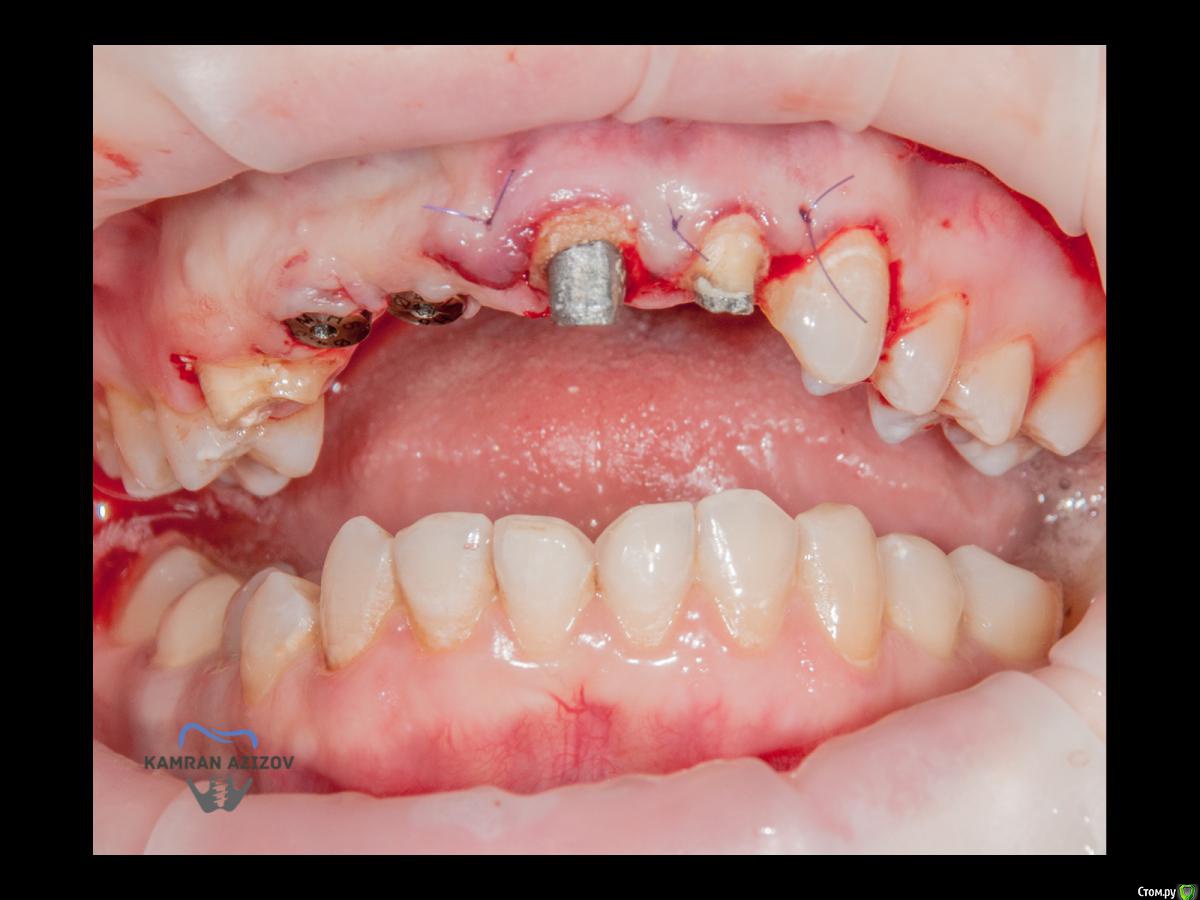

kamranchick Опубликовано 6 апреля, 2019 Поделиться Опубликовано 6 апреля, 2019 (изменено) Хай Гайсдавно ничего не комментировал и не выкладывал, что то настроения не было, да и муза не посещалаСитуация следующаяпришла пациентка, жалобы на неприятный запах из рта, сначала не понял что за хрень, ну как распилил мост понял че к чему... халтура.Ну и по кейсуУдаление клыка и 2ки, через 2 месяца навигация, имплантация + Шашлыки по карлоссу, смена формиков, временное протезирование. только мягкие ткани, Изменено 6 апреля, 2019 пользователем kamranchick 7 1 Ссылка на комментарий

Nazim_NV86 Опубликовано 7 апреля, 2019 Поделиться Опубликовано 7 апреля, 2019 Пятый Без пина шаблон не держался? Ссылка на комментарий

kamranchick Опубликовано 8 апреля, 2019 Автор Поделиться Опубликовано 8 апреля, 2019 Пятый Без пина шаблон не держался? держался) но сделали на всякий случай) Ссылка на комментарий